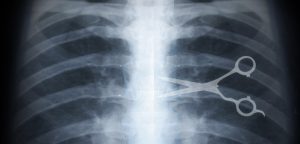

Some surgical negligence types are even labelled as “Never Events” due to their severity, but similar cases are still recorded. In fact, the NHS reported a whopping 190 Never Events in 2015 alone.

Taking a closer look at the common cases of surgical negligence. There are several major types to look out for. Having the wrong operation performed, the wrong part of the body operated on, or foreign objects left inside the body after an operation are the most common types of surgical negligence. You can get a medical negligence UK solicitor to assist you with your claim in any of these situations.